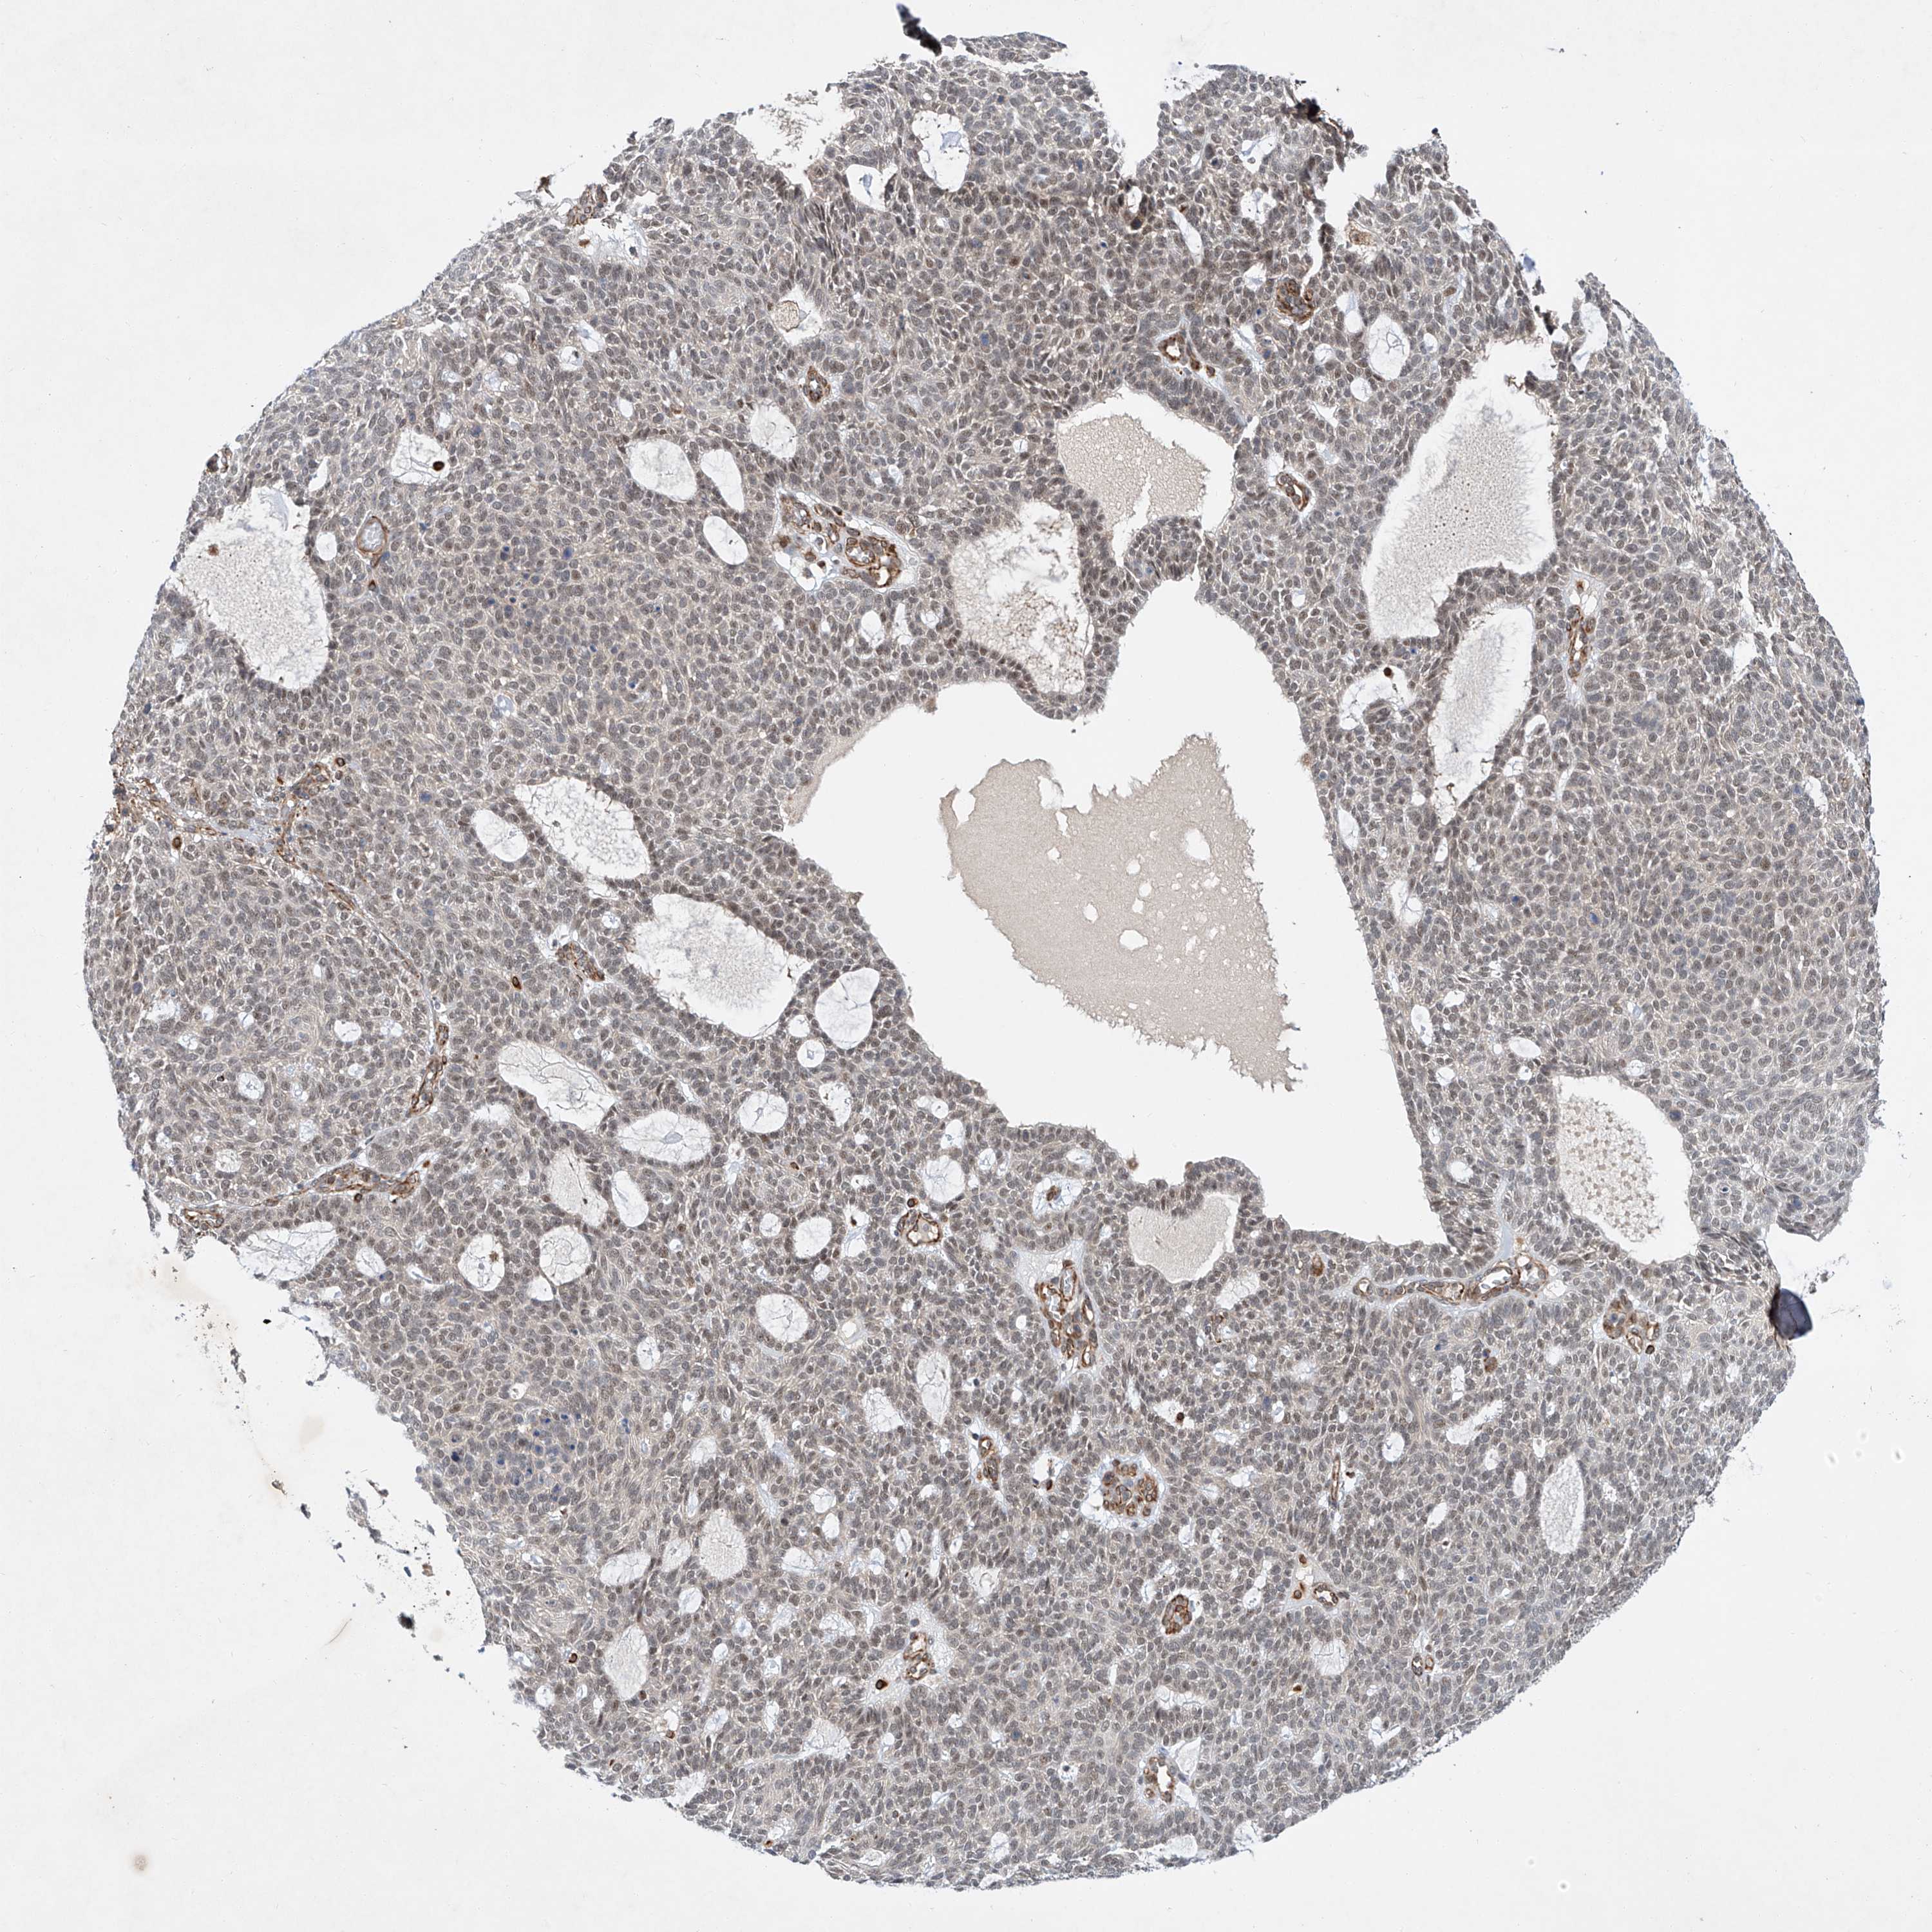

SKIN CANCER - Protein expressioni

A mouse-over function shows sample information and annotation data. Click on an image to view it in a full screen mode. Samples can be filtered based on level of antibody staining by selecting one or several of the following categories: high, medium, low and not detected. The assay and annotation is described here.

Antibody stainingi

Antibody staining in the annotated cell types in the current human tissue is reported as not detected, low, medium, or high, based on conventional immunohistochemistry profiling in selected tissues. This score is based on the combination of the staining intensity and fraction of stained cells.

Each image is clickable and will lead to virtual microscopy that enables deeper exploration of all samples and also displays staining intensity scores, fraction scores and subcellular localization as well as patient and tissue information for each sample.

Antibody HPA029281

Basal cell carcinoma